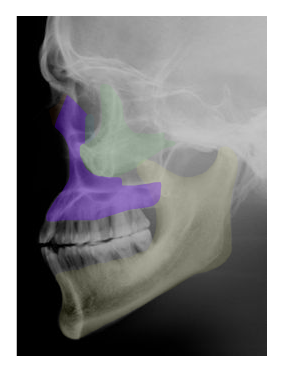

Cranial and Facial Bones

Students will use images and descriptions to reinforce their knowledge of the cranial and facial bones.

in red,  | VOMER |

| LACRIMAL |

| ZYGOMATIC |

| INFERIOR NASAL CONCHA |

| MAXILLA |

in orange,  | NASAL |

forms the "roof" of the mouth | PALATINE |

| FRONTAL |

| SPHENOID |

in purple,  | TEMPORAL |